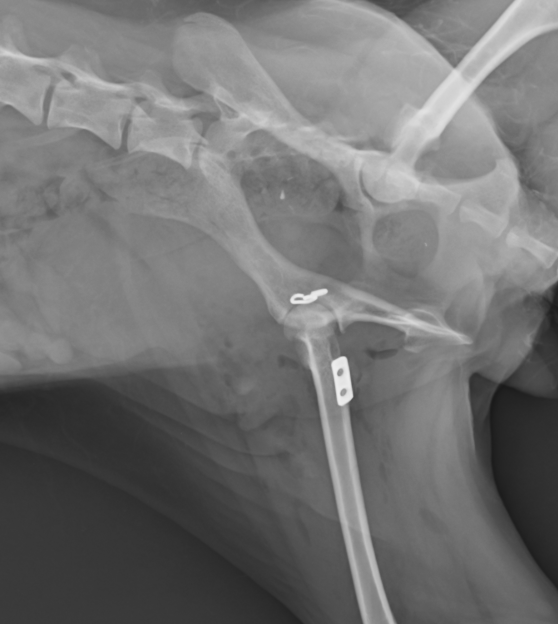

今回はトグルピン法という方法でもとに戻した症例です。症例はトイプードル10ヶ月で、ジャンプしているうちに足を痛がって挙げているとのことで来院されました。レントゲンで前上方脱臼が認められ手術を行いました。

術後のレントゲンです。白く写っているのは金属です。金属と金属の間にワイヤー(レントゲンには写りません)が通っており、骨頭が抜けないように引っ張っています。

骨頭がはまっているのがわかるかと思います。

術後すぐから足をついて立ち上がることが可能でした。2週間はこのまま安静にし、2週間脱臼が起きなければひとまず大丈夫であることが多いです。